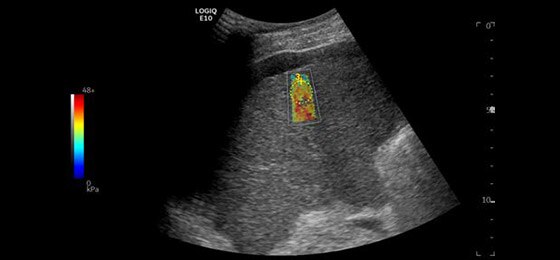

Liver Shear Wave Elastography, C1-6-D

2D Shear Wave Elastography quantifies tissue elasticity and provides color-coded elastograms.